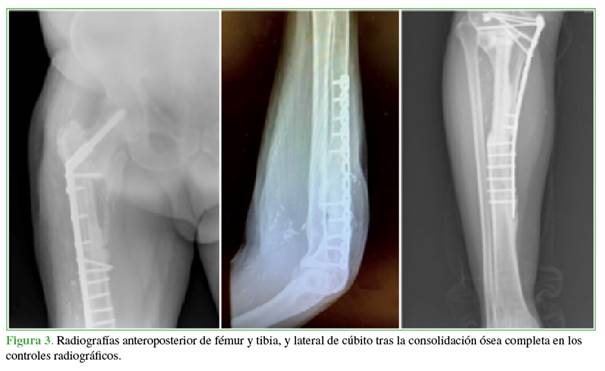

Las complicaciones quirúrgicas en la zona receptora fueron: una dehiscencia de la herida, una rotura del material de osteosíntesis, un paciente con consolidación viciosa y posteriormente una fractura patológica y dos casos de seudoartrosis.

El paciente con consolidación viciosa en varo fue sometido al año a una osteotomía correctora valguizante tibial proximal y fijación con placa atornillada (Figura 4). La fractura patológica se produjo a los tres años de la operación inicial de CVP y fue tratada con reducción abierta, autoinjerto de hueso y una placa de carbono.